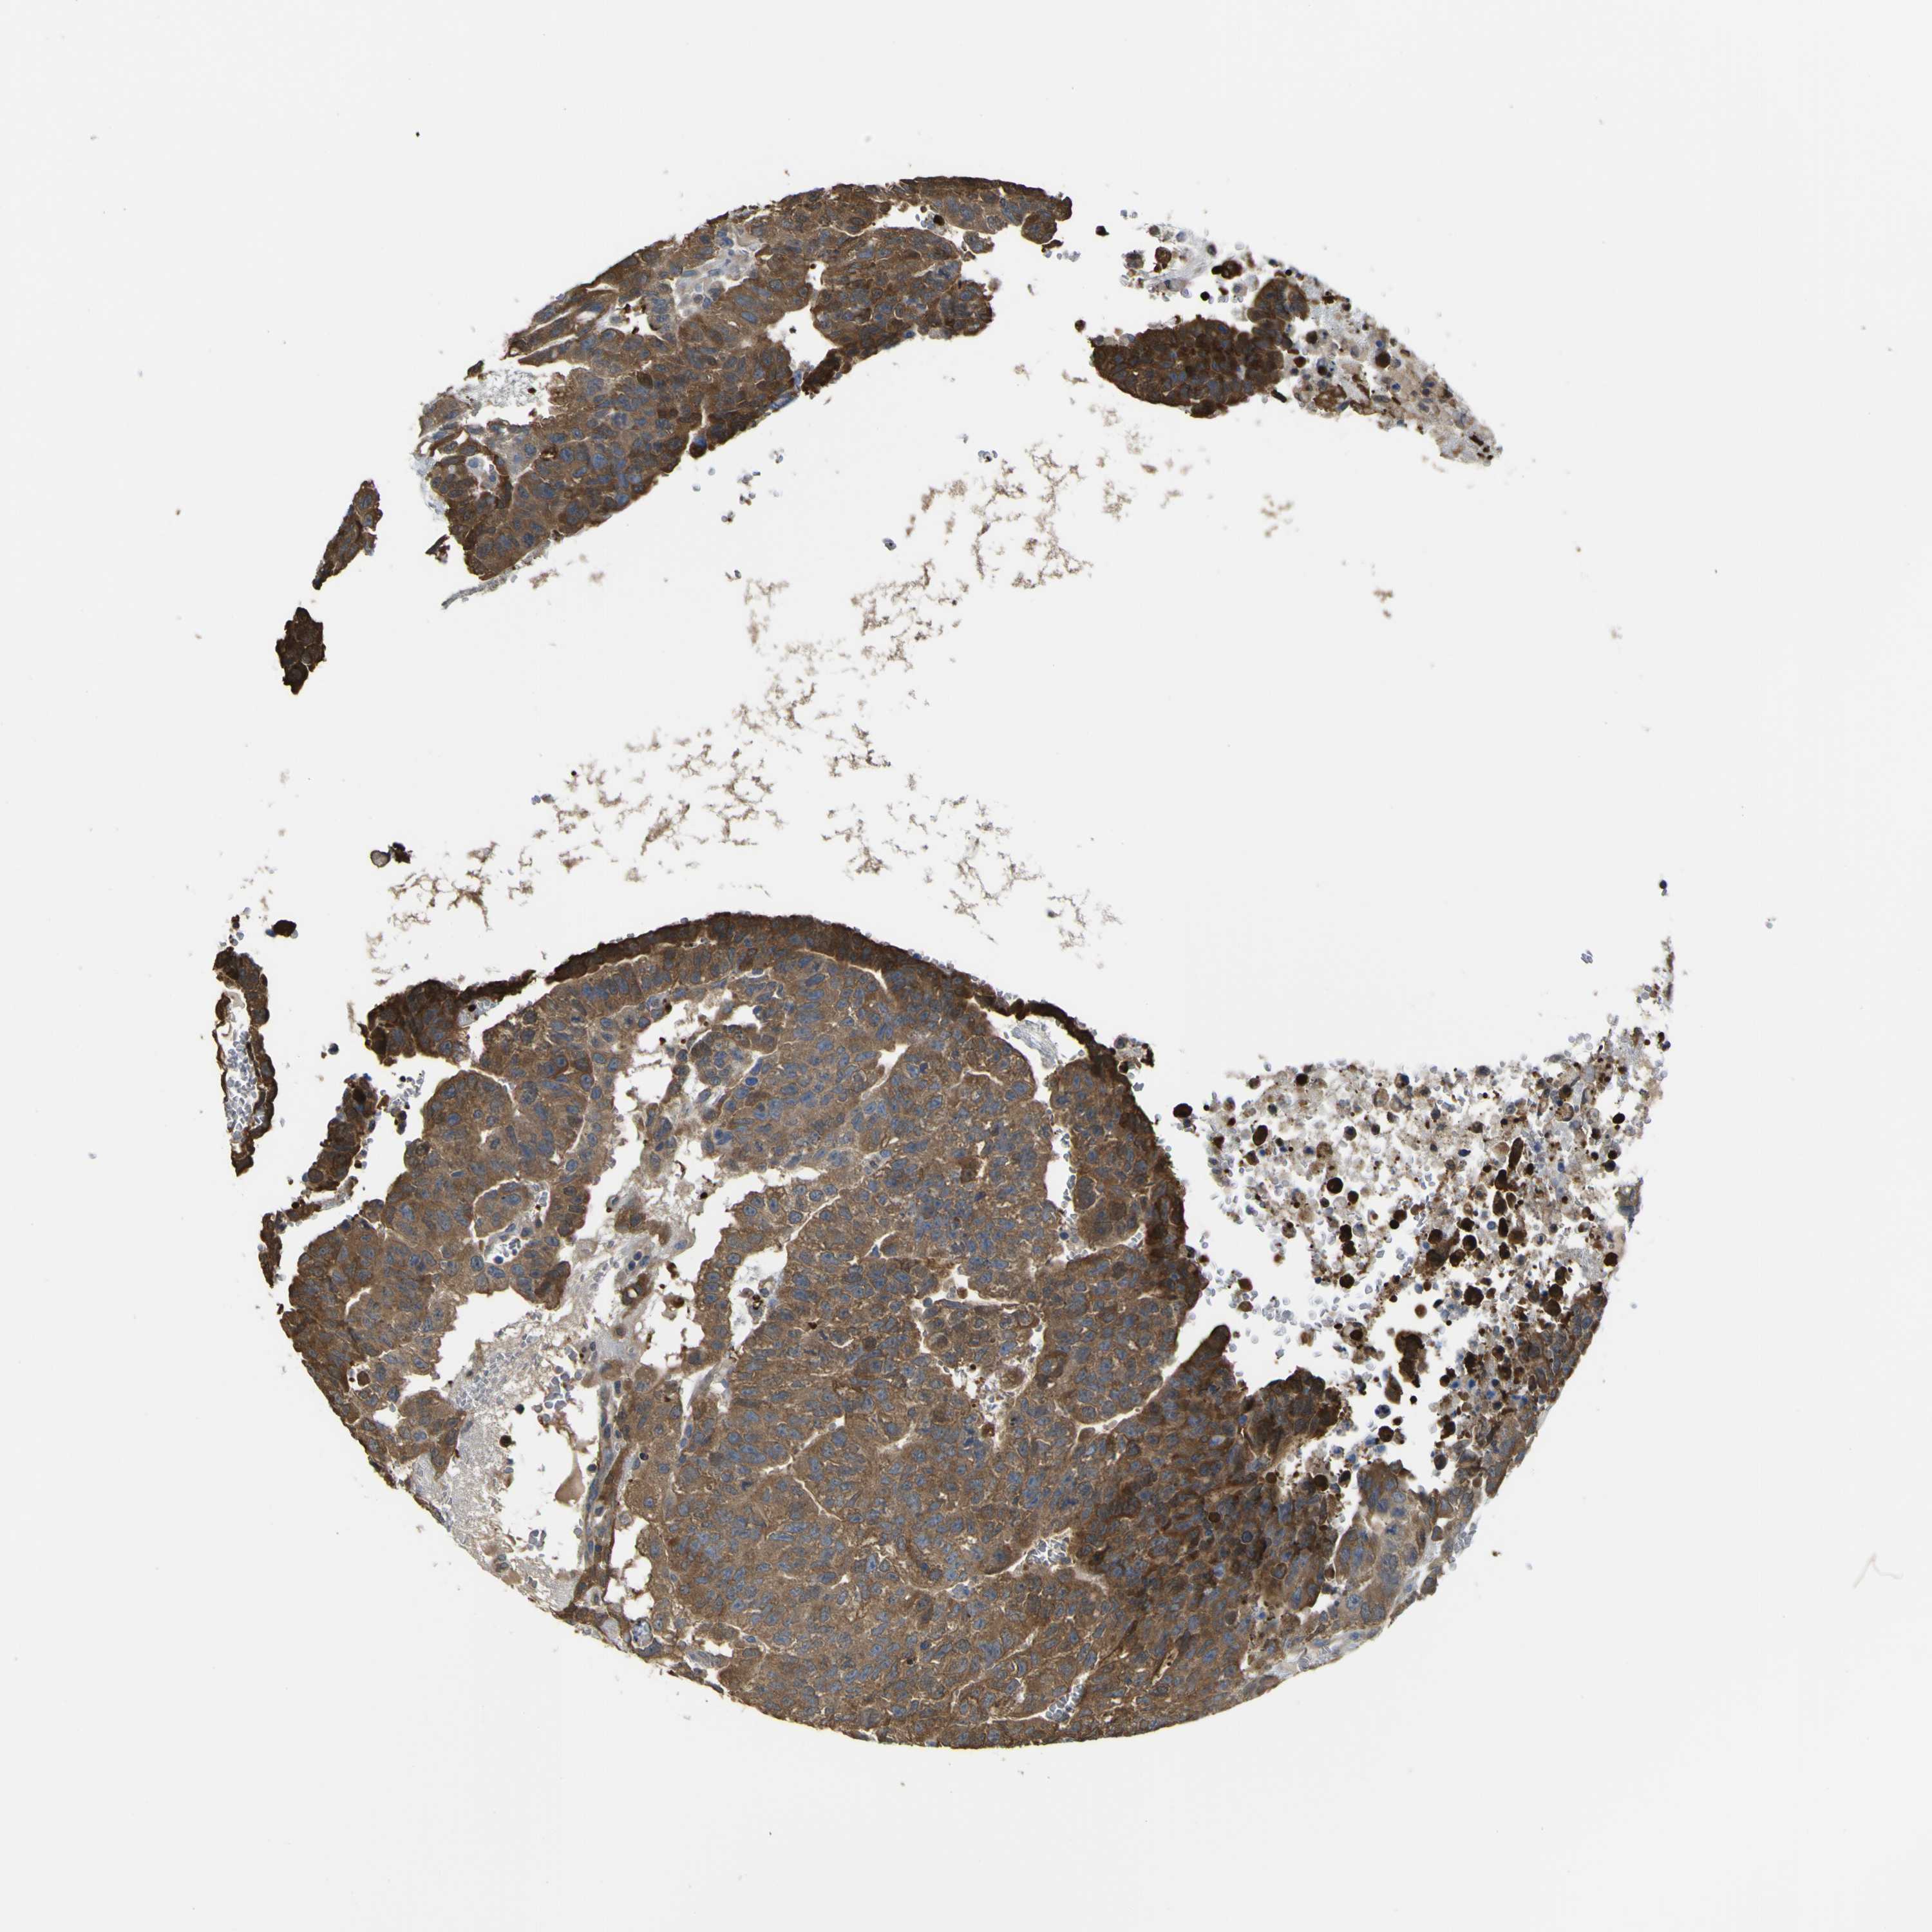

TESTIS CANCER - Protein expressioni

A mouse-over function shows sample information and annotation data. Click on an image to view it in a full screen mode. Samples can be filtered based on level of antibody staining by selecting one or several of the following categories: high, medium, low and not detected. The assay and annotation is described here.

Note that samples used for immunohistochemistry by the Human Protein Atlas do not correspond to samples in the TCGA dataset.

Antibody stainingi

Antibody staining in the annotated cell types in the current human tissue is reported as not detected, low, medium, or high, based on conventional immunohistochemistry profiling in selected tissues. This score is based on the combination of the staining intensity and fraction of stained cells.

Each image is clickable and will lead to virtual microscopy that enables deeper exploration of all samples and also displays staining intensity scores, fraction scores and subcellular localization as well as patient and tissue information for each sample.

Antibody HPA010729

Staining

High

Medium

Low

Not detected

Intensity

Strong

Moderate

Weak

Negative

Quantity

>75%

75%-25%

<25%

None

Location

Nuclear

Cytoplasmic/membranous

Cytoplasmic/membranous,nuclear

Carcinoma, Embryonal, NOS

Seminoma, NOS